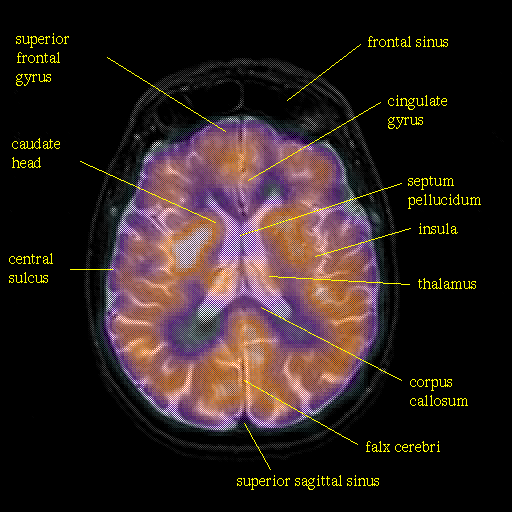

overlay: Slice 31

Slice 31

Pointers

Labeled

[Whole Brain Atlas Home Page] [Brain structure list] [Navigator Help Page]

Keith A. Johnson (keith@bwh.harvard.edu), J. Alex Becker (jabecker@mit.edu)